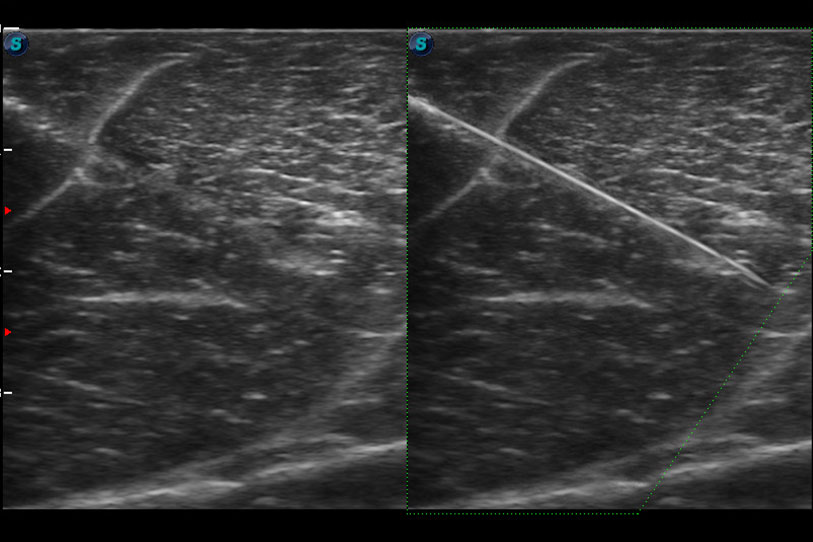

增强穿刺针在动物解剖结构中的位置,提高穿刺介入的安全性和准确性。